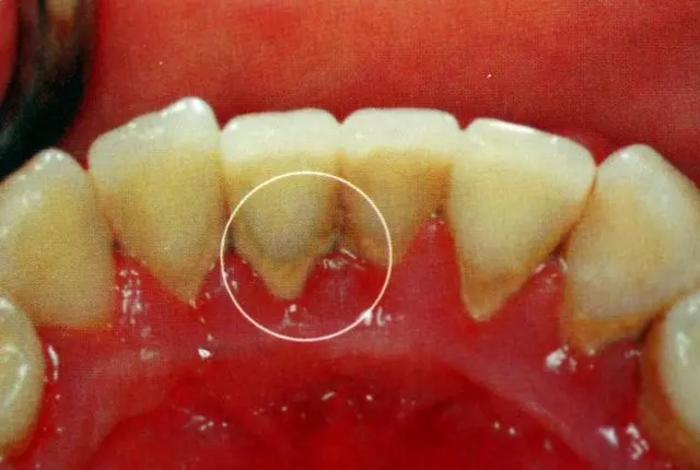

举个例子就知道啦!下图标注的A、B两颗牙齿表面看上去都没什么特别严重的问题

但是其中脱落的B牙却是这样的:

估计很多人都觉得不可思议,觉得这两颗牙看着都没那么脏啊?看着不脏,龈下却已经积满牙结石。